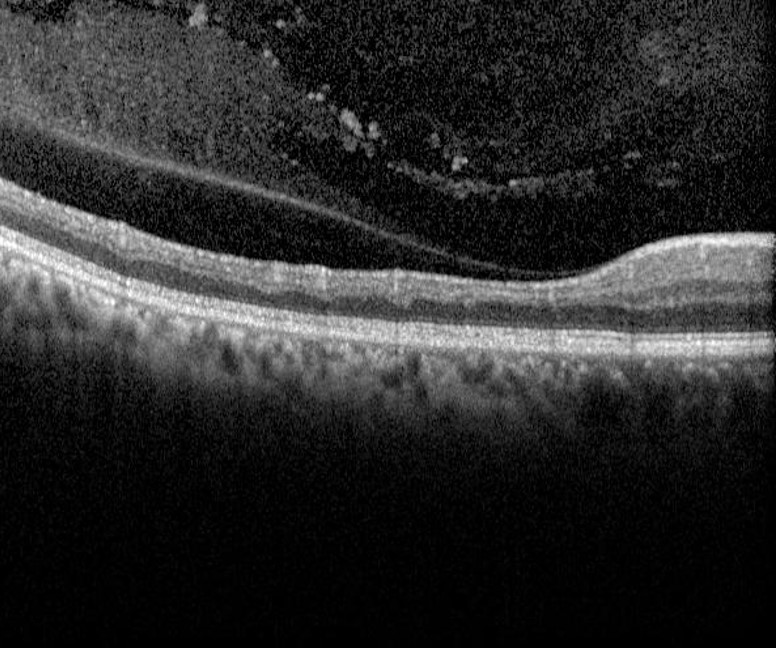

Retinal oedema, seen on OCT as a thickening of the inner retinal layers, is associated with acute retinal arterial occlusion.

Over time, a chronic arterial occlusion results in atrophy and loss of the inner retinal layers which can be detected with OCT imaging. Neovascularisation is very rare in all forms of retinal arterial occlusion.